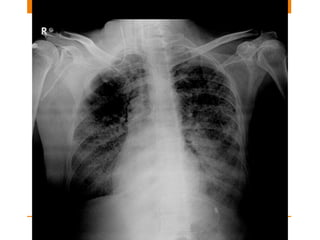

Swartz Ganz Catheter

• Also known as pulmonary arterial line commonly

• To assess left atrial pressure and cardiac output

• Very important in ICU patients to distinguish between

cardiac and non cardiac pulmonary edema

• Now a days not much in use in regard with patient

outcome